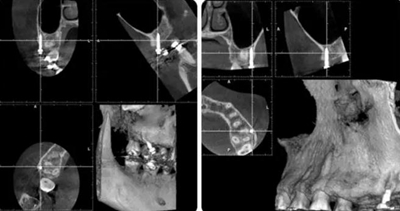

治療8個月,換0.018*0.025"CuNiTi弓絲,植入支抗釘,植入位點(diǎn)為上頜第一磨牙根上方顴牙槽嵴處,使其與牙根平行。同時嘗試性牽引遠(yuǎn)移上牙列。

(3)全牙列遠(yuǎn)移種植釘植入位點(diǎn)為上頜第一磨牙根上方顴牙槽嵴處,使其與牙根平行,在術(shù)前需CBCT確認(rèn)骨量,否則有脫落或無法植入的可能。